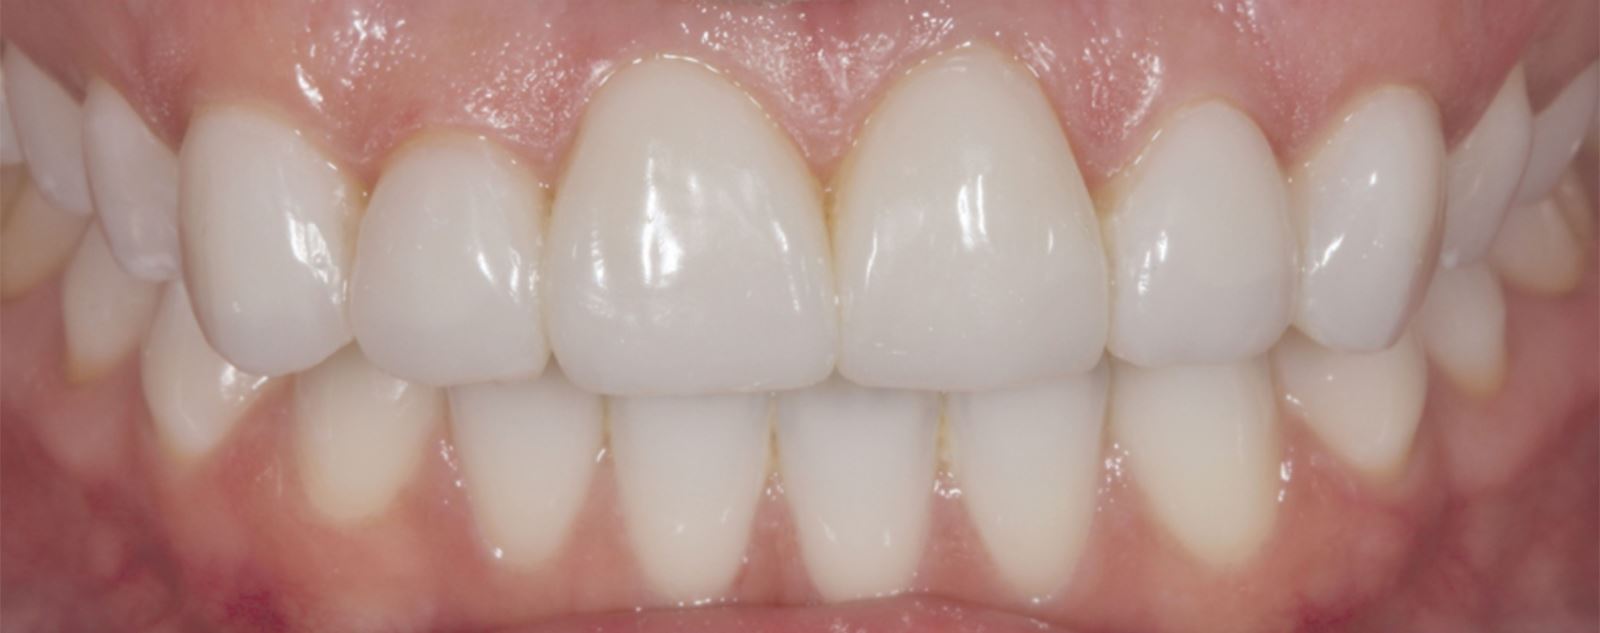

Výsledek a závěrečné zhodnocení

Tento postup úspěšně vyřešil estetické obavy pacientky překrytím diskolorace horních frontálních zubů a dosažením přirozeného, vyváženého vzhledu ve vztahu k dolním frontám. Použití kompozitních fazet bez preparace poskytlo konzervativní, vysoce efektivní řešení, které respektovalo finanční možnosti pacientky a její požadavek na minimálně invazivní přístup.